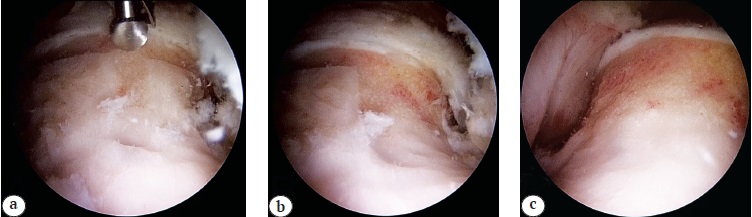

Вариантом комбинированной вне- и внутрисуставной патологии переднего отдела ТБС, сопутствующей ФАИ и выявленной по МРТ, является импинджмент-синдром m. psoas, сочетанный с внутрисуставным повреждением суставной губы и возможным наличием илиопектинальной бурсы или отека переднего края вертлужной впадины [84] (рис. 8, 9). Также стоит обратить внимание на строение сухожилия m. psoas, имеющее в 17% случаев две и более части, сохранение которых при тенотомии может повлечь рецидив импинджмента [85].

Рис. 8. Разрыв губы вертлужной впадины (белая стрелка) с формированием кисты (черная стрелка)

Fig. 8. Acetabulum labrum rupture (white arrow) with cyst formation (black arrow)

Рис. 9. Отек переднего края вертлужной впадины (черная стрелка) в проекции сухожилия m. psoas (белая стрелка)

Fig. 9. Edema of acetabulum anterior edge (black arrow) in the projection of tendon m. psoas (white arrow)